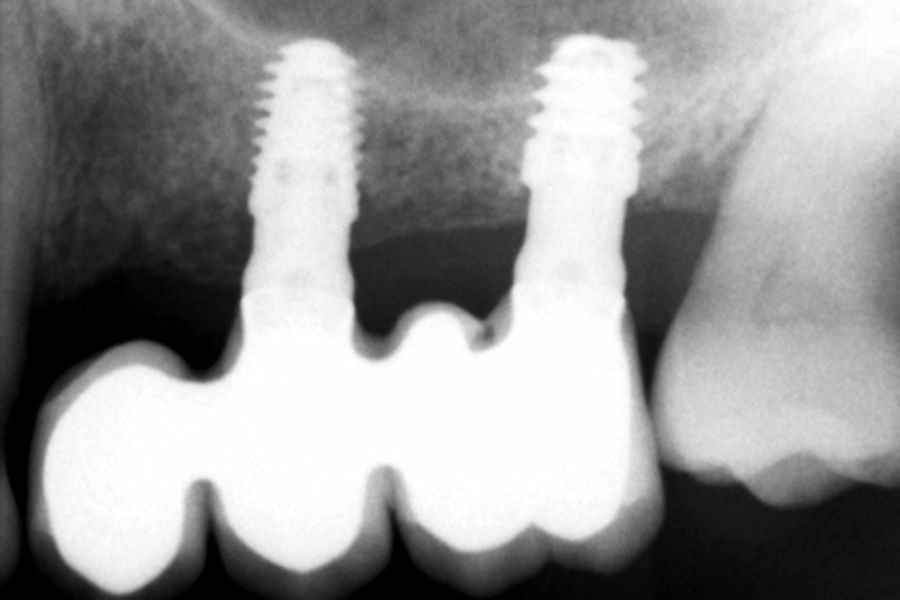

Como primer paso, se realiza un escaneado intraoral de la paciente, para poder generar un encerado virtual con las piezas que queremos rehabilitar con implantes (Figuras 6-8). Esto nos permite planificar con claridad el caso y desde el modelo tridimensional, generar los provisionales y las guías quirúrgicas basadas en la posición protésica, que desde el flujo digital pueden imprimirse (Figuras 9-14). Desde el encerado podemos además generar otras guías, en este caso radiológicas, con las que realizar el Cone-Beam Computed Tomography (CBCT) de planificación. Con esta información tenemos en el mismo estudio radiológico la fusión de nuestra planificación quirúrgica y la posición real de la prótesis adaptada a la oclusión, muy útil para generar una planificación que contempla todos los parámetros. En este caso, se planifican implantes cortos de 6,5 mm en el primer cuadrante, de morfología Core-Xâ, para lograr una correcta estabilidad primaria en un tipo óseo IV como vemos en el corte seccional (Figuras 15 y 16). En el segundo cuadrante, con similares características, planificamos implantes de 6,5 y 5,5 mm de longitud (Figuras 17 y 18).

El fresado de este tipo de implantes, al basarse en la oseodensificación en toda la longitud, se realiza a menor diámetro, en dos tramos, uno para el cuerpo del implante y otro para el ápice, que siempre tiene una mayor capacidad de penetración y menor diámetro. Para una situación de hueso tipo IV/V en el maxilar , fresaremos hasta 2,8 mm en la zona del cuerpo y a longitud de 1,8 mm para el ápice, lo que se corresponde con la fresa piloto. Con ello al insertar el implante generamos una compresión lateral que produce una mayor estabilidad primaria en estas zonas de baja densidad (Figuras 19 y 20). Una vez colocado el implante, todo el hueso que le rodea, circunferencialmente alcanza una mayor densidad, lo que produce que la estabilización sea mayor en toda su superficie (Figuras 21 y 22). Si realizamos una comparativa entre el volumen condensado mediante la colocación de un implante convencional y uno de la morfología Core-Xâ, se observa la diferencia entre el cuerpo del implante y el fresado, lo que nos da una idea de la diferencia en la consecución de la estabilidad primaria (Figuras 23 y 24).

Transcurridos 6 meses desde la carga inicial progresiva, se puede elaborar la prótesis definitiva, trasladando los parámetros de la prótesis provisional (Figura 27). La paciente continúa en seguimiento durante un año, realizándose radiografías de control para el monitoreo del hueso crestal, sin encontrarse pérdida ósea asociada en ninguno de los implantes (Figuras 28-29).